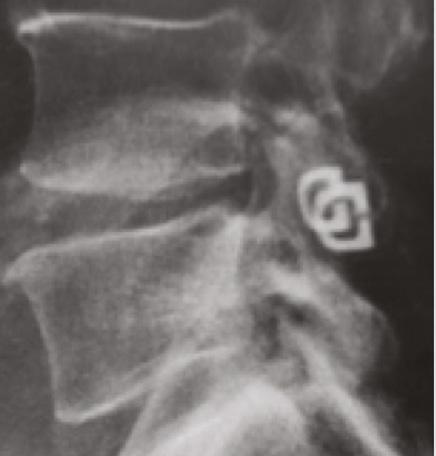

PROMO/MAG/GL/048-22/R00Reference: 1. Data on File. Manufactured by Kuros Biosciences BV Prof Bronkhorstlaan 10, Building 48, 3723 MB Bilthoven, The Netherlands. kurosbio.com MagnetOs is a trademark of Kuros Biosciences. And our latest Project Fusion ndings look remarkable1 The Kuros team initiated a patient and observer-blinded, randomized, intra-patient controlled, multi-center clinical trial evaluating MagnetOs Granules as a standalone alternative to autograft in posterolateral fusion (PLF). The preliminary results for the rst 50 (of 100) subjects are now in and... Fusion rate by CT after one year: (% subjects) MagnetOs Granules achieved a fusion rate of 78% (39/50

MagnetOs Granules 78.0% (39/50)

Autograft 42.0% (21/50)

subjects) compared to 42.0% (21/50 subjects) for autograft.